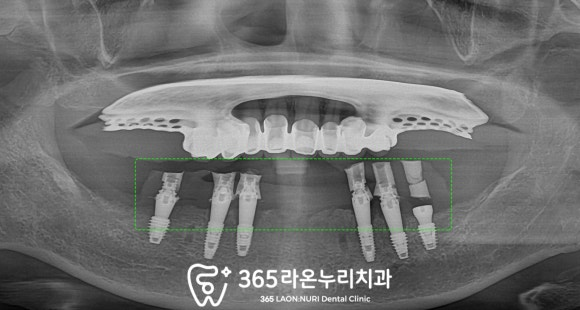

■ 2. 잔존 치근 발치 후 디지털 임플란트

우선 부러진 이는 염증을 키울 수 있으니 뽑고

하악은 최소 개수의 픽스처를 심어

기능을 재건해주기로 했습니다.

그런데 이렇게 얇은 치조골에

최소 개수만 식립한다는 것은

결코 쉬운일은 아닙니다.

그렇기에 ‘디지털 가이드’를 이용한

수술을 진행하기로 했는데요,

말 그대로 구강을 스캔한 정보를 토대로

픽스처가 단단히 심어질 위치를

사전에 계획할 수 있는 가이드를 만드는 것이죠.

다시 본론으로 돌아와

하치조신경을 고려하고

치조골의 두께 및 초기고정력에 유리한 곳에

총 6개의 픽스처를 심었습니다.